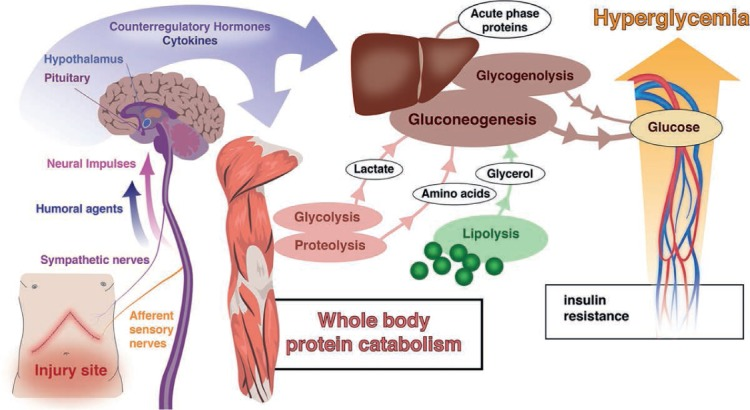

A cirurgia cardíaca representa a perfeita união entre maestria cirúrgica e tecnologia. Para operar um coração, é comum que sua…